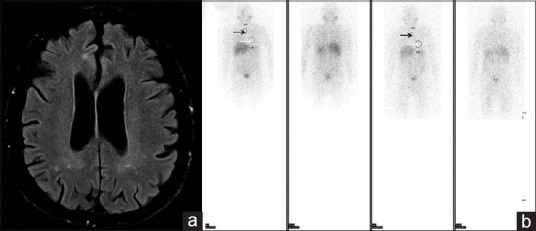

The Usefulness of 131 I-MIBG Myocardial Scintigraphy in a Case of Pure Autonomic Failure - First Report in the Literature.